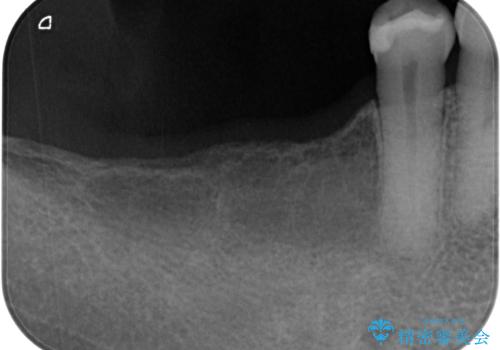

レントゲンで確認すると骨は十分にあるので通法通りインプラントによる補綴治療を行いました。